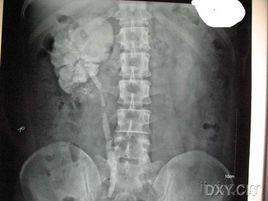

腎自截 腎自截為腎結核終末期病變,是泌尿繫結核的一種特殊病理類型,發生於極少數病人,此時輸尿管因結核侵蝕,完全阻塞,全腎在腎積水或積膿基礎上廣泛鈣化,混有乾酪樣物質,結核桿菌不能隨尿液流入膀胱,膀胱的繼髮結核病變反而好轉和癒合,症狀消失。腹部平片顯示病變腎不同程度鈣化,IVP檢查病變腎無造影劑充填,同側輸尿管未顯示。CT在平腎門水平可見花瓣狀或彎曲充盈腸腔樣鈣化,為CT診斷腎自截的典型特徵,可與腎腫瘤、腎囊腫及腎膿腫等引起的鈣化相鑑別。